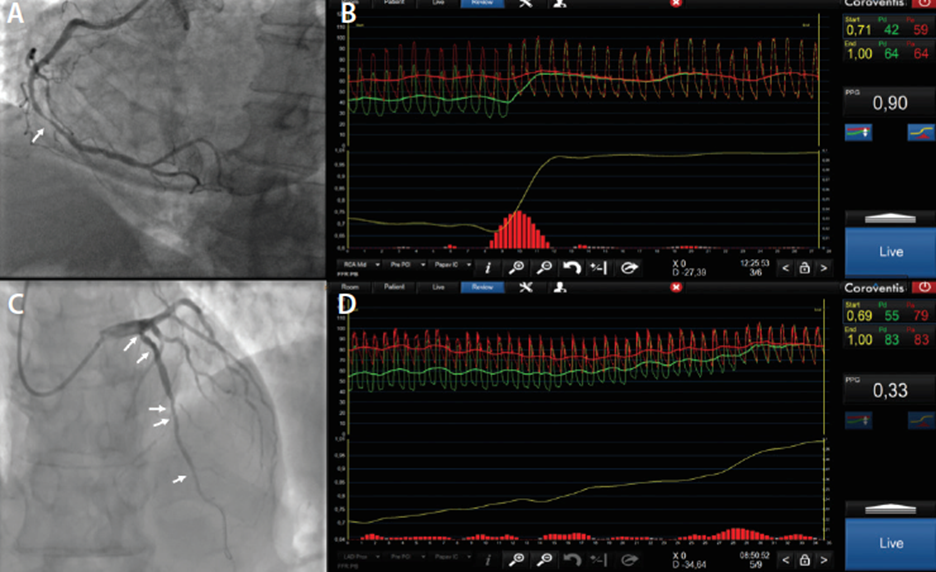

- Fisiologia coronária – FFR, iFR, RFR

Esta tecnologia permite avaliar o comportamento do fluxo de sangue através de placas nas artérias, o que ajuda o cardiologista a tomar uma decisão assertiva sobre que lesões devem ser tratadas.

À esquerda, lesões coronárias vistas no cateterismo e, à direita, as ondas de pressão representando o fluxo sanguíneo.